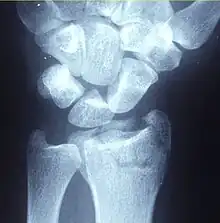

| Other names: Broken wrist[1] | |

| A Colles fracture as seen on X-ray: It is a type of distal radius fracture. | |